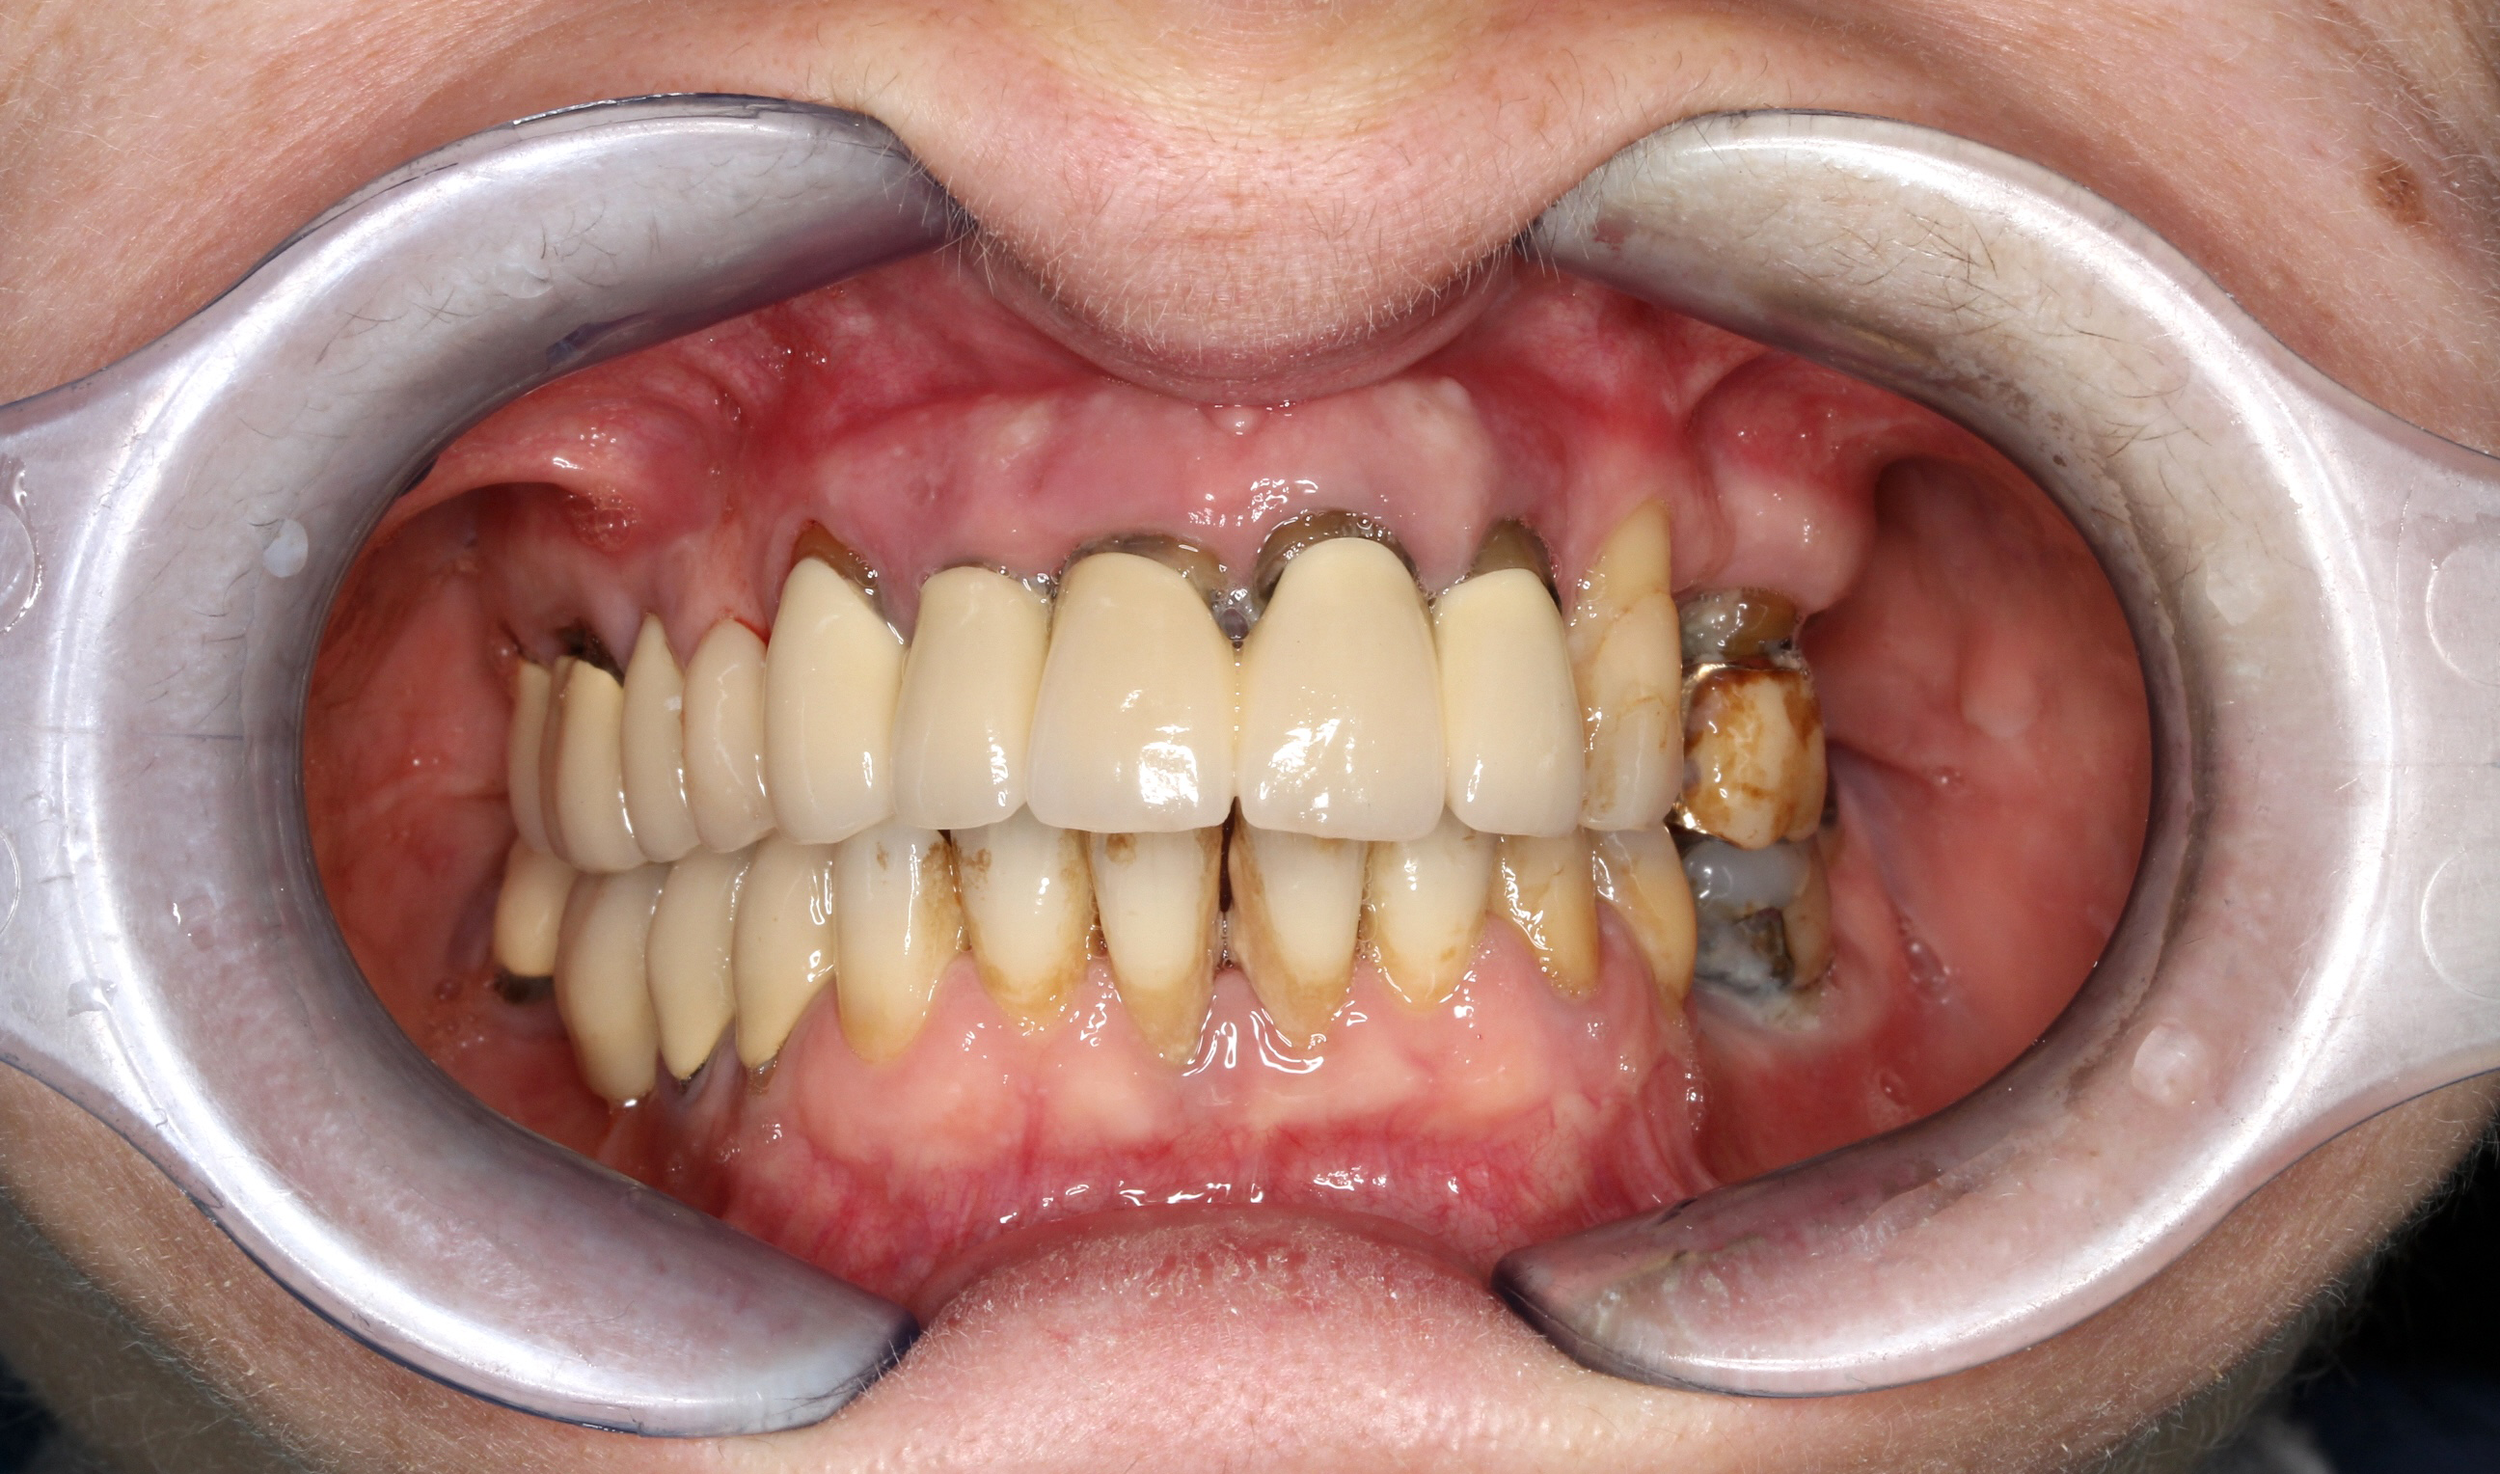

A causa di vari problemi di salute, la paziente si trova in una situazione di edentulia completa in entrambe le arcate. Le attuali protesi mobili sono per lei fonte di forte insicurezza a causa della loro mobilità. Nonostante la scarsità di osso mascellare e la presenza di viti di osteosintesi nella mandibola si procede con una riabilitazione fissa su entrambe le arcate combinando impianti tradizionali (mandibola) con impianti iuta-gengivali, nella mascella.

PRIMA